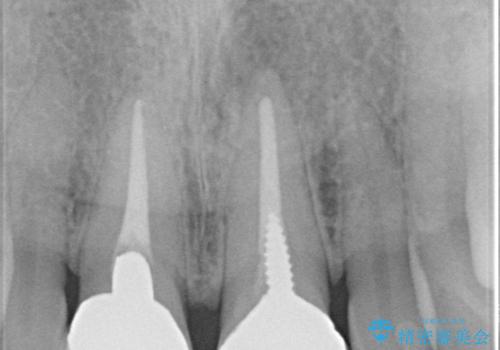

根管治療について

保険根管治療は回数がかかることが多く、終了予定がわかりにくいです。

当院では、根管治療は長い時間のご予約を頂き、多くの場合2~3回で終わります。

根管治療は歯内の治療なので患者様には見えない場所ですが、ここが細菌で汚染されると激しい痛みや長引く違和感の原因になります。

当院では、清潔な治療を徹底し、顕微鏡を使用した精密な治療を行っています。

症状や根管の状態により、治療金額が異なります(5~10万円目安)。治療回数による費用負担の増減はありません。

根管治療専門医をご紹介させて頂く場合がございます。